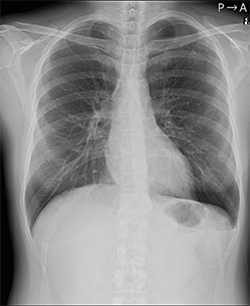

オリジナル画像 |

気胸の検出領域を表示 |